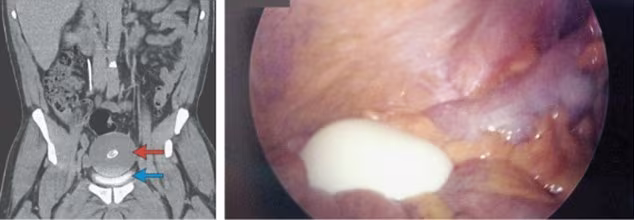

Phát hiện “quả trứng luộc” trong bàng quang một người đàn ông ảnh 1Hình ảnh của vật thể lạ trong bàng quang

Sau khi làm thủ tục khám và lấy các mẫu xét nghiệm gửi đến phòng thí nghiệm, các bác sĩ đã không tìm thấy gì khác thường trong cơ thể của người đàn ông. Tuy nhiên, họ đã sử dụng máy quét CT trong ổ bụng và phát hiện một vật thể lạ khổng lồ. “Nó tròn, vỏ mịn màng săn chắc, như một quả trứng bằng cao su, đang trôi nổi tự do trong bàng quang”, một bác sĩ mô tả.

Khối chất hình quả trứng đã được lấy ra từ cơ thể bệnh nhân sau phẫu thuật và cắt lớp để phân tích

Kết thúc cuộc phẫu thuật, các bác sĩ đã lấy ra được vật thể. Nó giống như một quả trứng luộc: dài đến 10cm, rộng 7,5 cm và nặng 220 g. Các bác sĩ cho biết đây là một dạng viêm bờm mỡ đại tràng (Epiploic  Appendages), túi mỡ bọc trong màng đại tràng tách ra, trôi nổi trong cơ thể và sẽ biến đổi thành một cục xơ khi bị vôi hóa.

Các bác sĩ cũng nói thêm rằng đây là trường hợp một túi mỡ viêm hình thành lớn nhất từ trước tới nay, các trường hợp phát hiện ra túi mỡ rộng hơn 5cm được coi là rất hiếm. Sau đó, các bác sĩ đã nhuộm mực xanh lên khối chất lấy từ cơ thể bệnh nhân để cắt lớp và phân tích nó. Nó chứa một lớp mô xơ, lớp protein, một lớp mô bị vôi hóa và trung tâm là chất xơ.